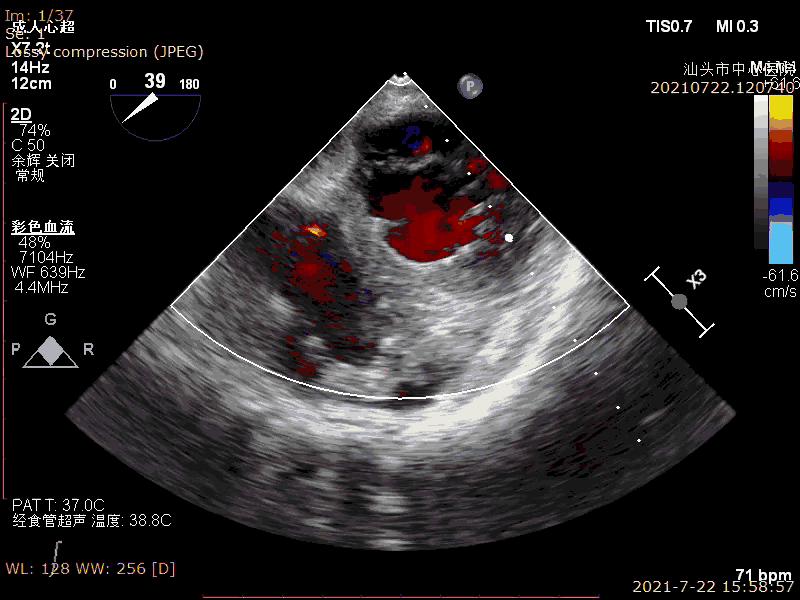

术后超声

轻微反流,压差降低